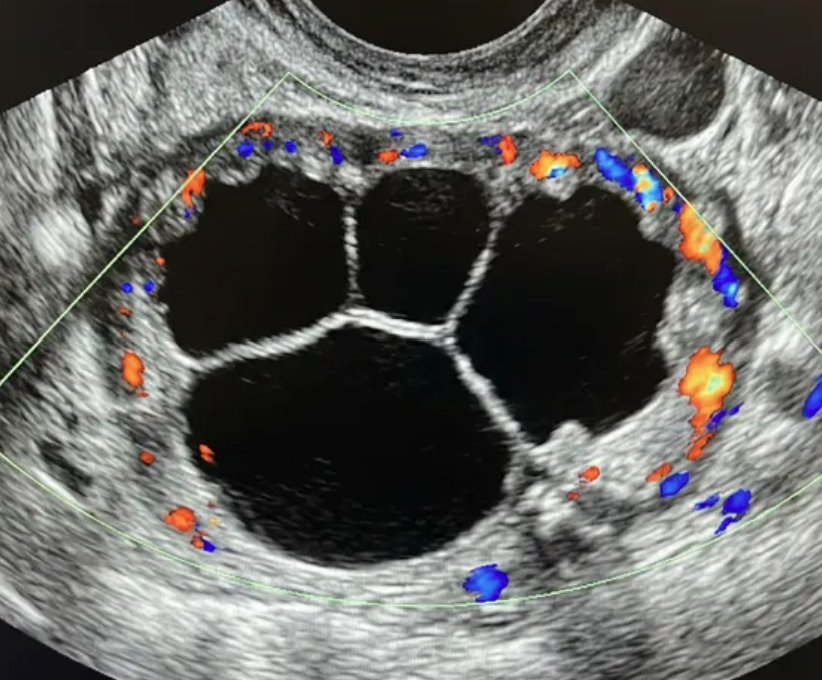

Risco: 10-<50%Cisto multilocular sem componente sólido ≥ 10 cm ou com IC = 4, cisto unilocular/multilocular com componente sólido, lesão sólida com superfície lisa e IC = 2–3.

Cisto multilocular, sem componente sólido

Opções de imagem incluem US com especialista (se disponível) e RM (com O-RADS MRI score), de acordo com o protocolo do ginecologista-oncologista. Atendimento pelo ginecologista com consulta ao ginecologista-oncologista ou exclusivamente pelo ginecologista-oncologista.